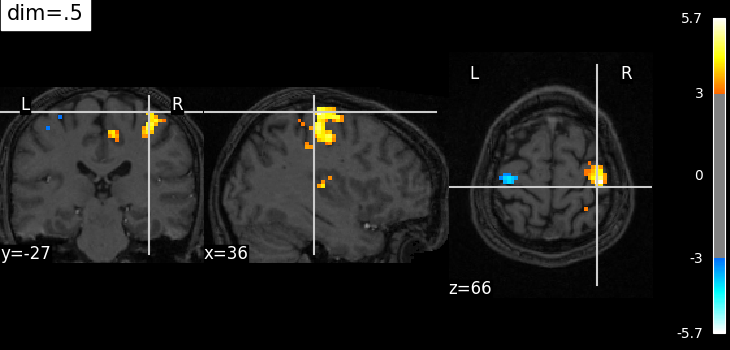

The dim argument controls the contrast of the background.

dim modifies the contrast of this image: dim=0 leaves the image unchanged, negative values of dim enhance it, and positive values decrease it (dim the background).

Plotting with decrease of contrast in background image with dim=.5¶

plotting.plot_stat_map(

localizer_tmap_filename,

bg_img=localizer_anat_filename,

cut_coords=(36, -27, 66),

threshold=3,

title="dim=.5",

dim=0.5,

)

<nilearn.plotting.displays._slicers.OrthoSlicer object at 0x7f3bd0a03b30>